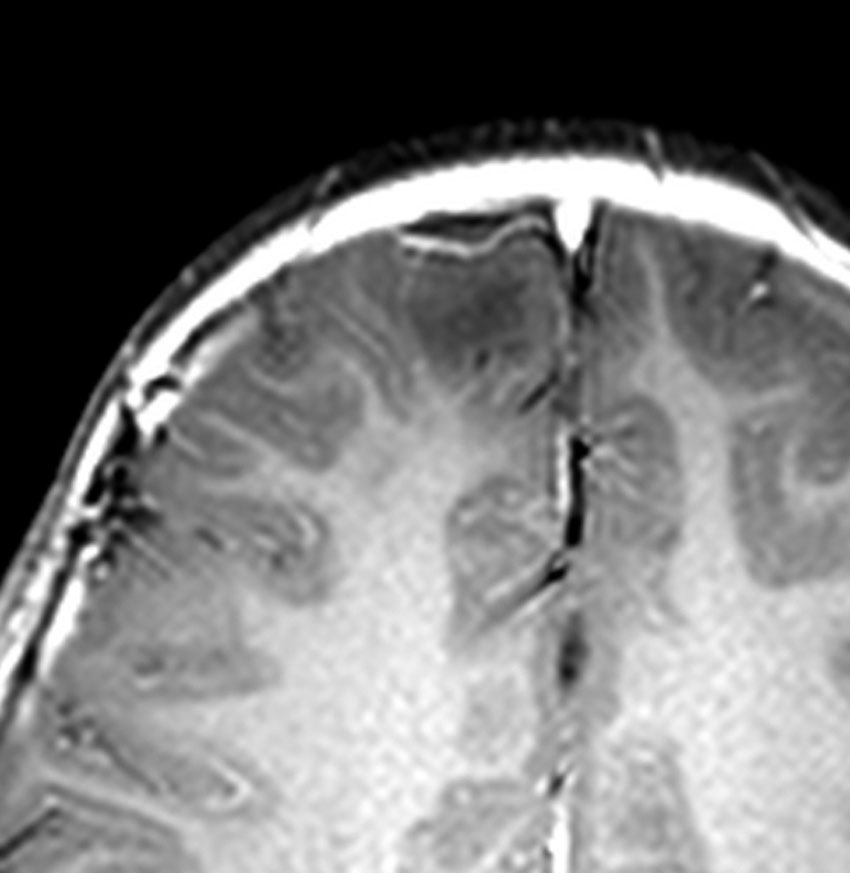

摘出して8年後のMRIです。手術後に発作は完全に消失してmedication freeです。発症後3年で手術摘出したのですが,間に合ったのでしょう。薬物治療を続けて発作期間が長期化してから手術摘出すると単なる病変切除ではてんかんが制御できないことがあります。